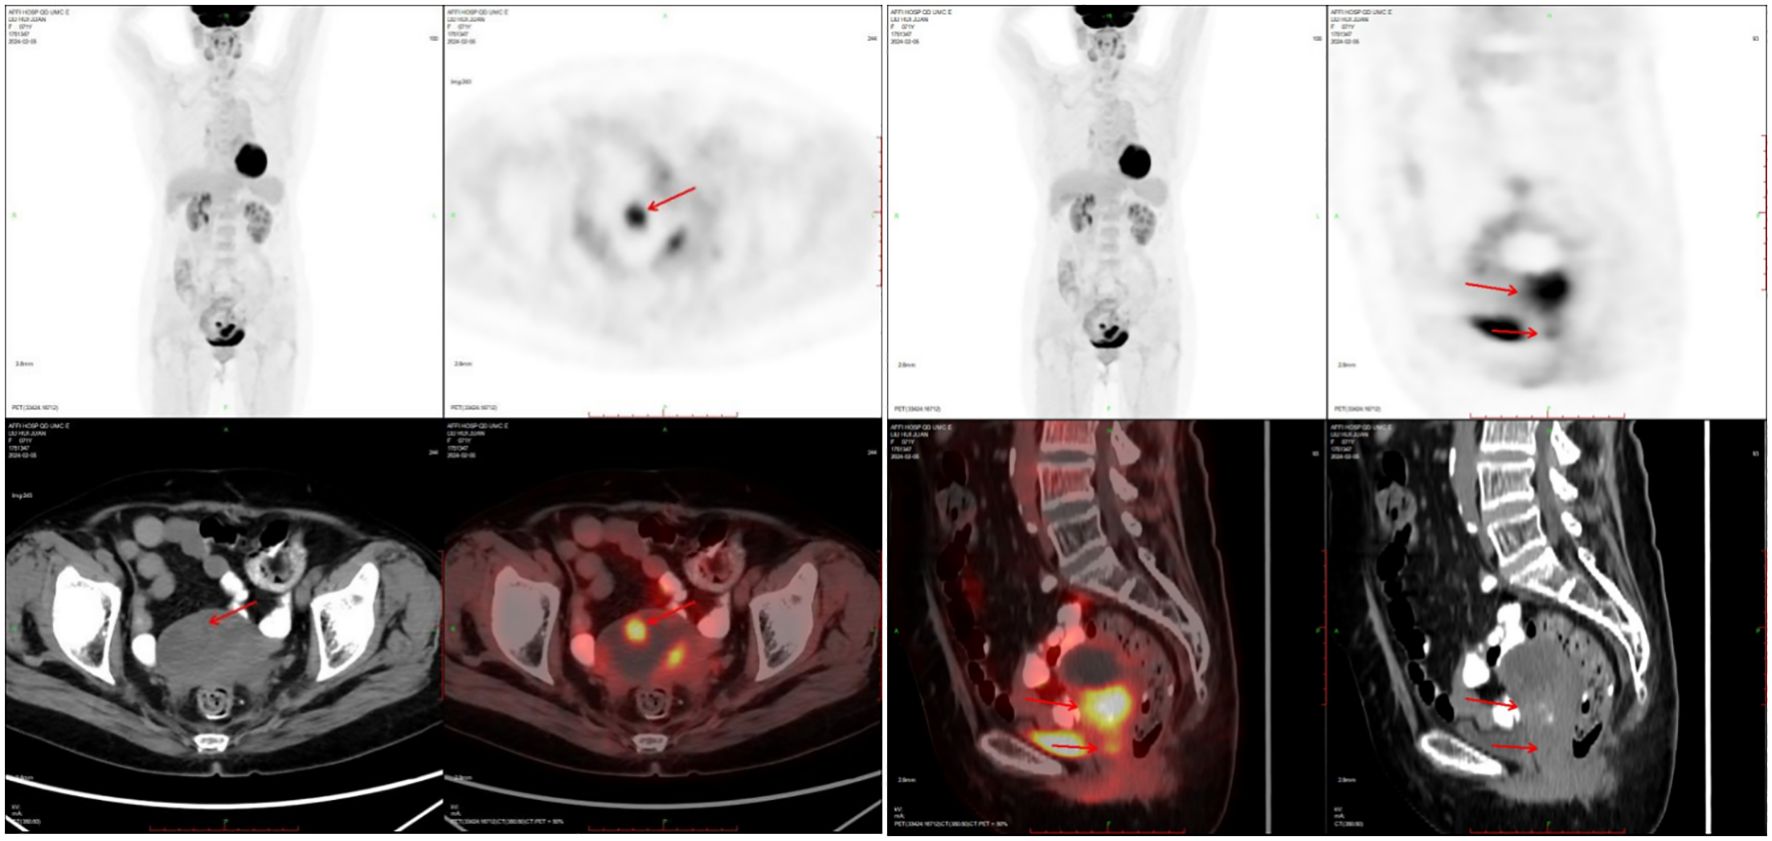

A 71-year-old postmenopausal woman presented with scant dark-red vaginal bleeding. She sought medical treatment at Qingdao University Affiliated Hospital. B-ultrasound revealed an enhanced echo in the lower uterine segment, measuring approximately 5.6×4.8×3.8 cm, raising suspicion of endometrial carcinoma (Figure 1). Diagnostic endometrial biopsy subsequently confirmed adenocarcinoma, favoring endometrioid subtype. Serum tumor markers were as follows: Alpha-fetoprotein (AFP) 15.480 ng/mL (reference range: 0–7 ng/mL), carcinoembryonic antigen (CEA) 8.070 ng/mL (reference range: 0–5 ng/mL), carbohydrate antigen 199 (CA199) 98.280 U/mL (reference range: 0–30 U/mL), and carbohydrate antigen 125 (CA125) 8.080 U/mL (reference range: 0–25 U/mL). Whole-body PET/CT demonstrated an ill-defined hypermetabolic soft-tissue nodule (SUVmax ≈13.8) in the uterine corpus-cervix junction and an intracavitary protruding nodule (SUVmax ≈9.3) in the fundus, with no enlarged lymph nodes in the bilateral iliac/inguinal regions, consistent with uterine malignancy (Figure 2). Following an initial diagnosis of endometrial malignancy, the patient was admitted to our gynecology department on February 16, 2024, for surgery. Following admission, a comprehensive medical history was documented. The patient is G3P2A1. Fourteen years ago, she underwent surgical treatment for rectal cancer, followed by adjuvant chemoradiotherapy. Regular postoperative surveillance revealed no signs of recurrence. On February 20, 2024, the patient underwent laparoscopic exploration Laparoscopy revealed dense adhesions between the rectum/sigmoid colon and left pelvic wall, with fibrosis impeding vascular dissection. Frozen section pathology indicated moderately-to-poorly differentiated adenocarcinoma with necrosis and calcification, infiltrating nearly the full myometrial thickness. Consequently, we performed laparoscopic extrafascial total hysterectomy, bilateral adnexectomy, right pelvic lymph node dissection, para-aortic lymph node biopsy, and pelvic adhesion lysis.

Figure 2. PET-CT showed nodules of soft tissue density at the base of the uterine body, protruding intrauterine, with increased metabolism, which was consistent with malignant uterine tumors.